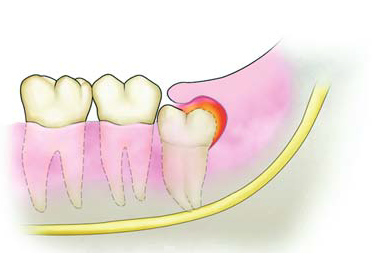

2、 急性智齿冠周炎

这是因为智齿萌出的位置不正确,导致了牙齿面把牙龈覆盖住了,这样容易引起食物嵌塞,容易造成细菌的滋生,最终导致炎症的发作,会出现牙龈肿痛、疼痛。